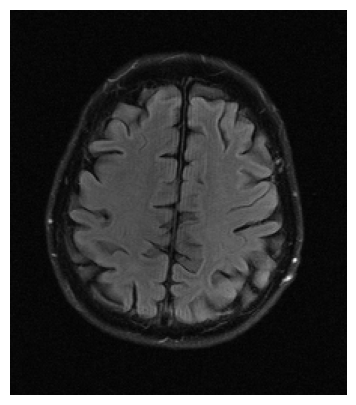

Qualitative.

The visual inspection of the images reconstructed (available in Fig. 2) at acceleration factor 4 shows little to no visible difference with the ground truth original image. However, when increasing the acceleration factor to 8, we can see that smoothing starts to appear which leads to a loss of structure as can be seen in Fig. 3.

| T1 PSNR: 41.56 SSIM: 0.9506 | T2 PSNR: 40.68 SSIM: 0.9554 | FLAIR PSNR: 39.60 SSIM: 0.9321 | T1POST PSNR: 42.53 SSIM: 0.9683 |